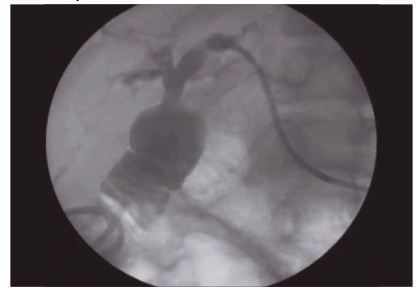

Evolucionó de forma favorable y dos semanas después se realizó una nueva colangiografía percutánea, donde se observó la ausencia de imágenes negativas en la vía biliar, por lo que se retiró el drenaje percutáneo (Figura 3).